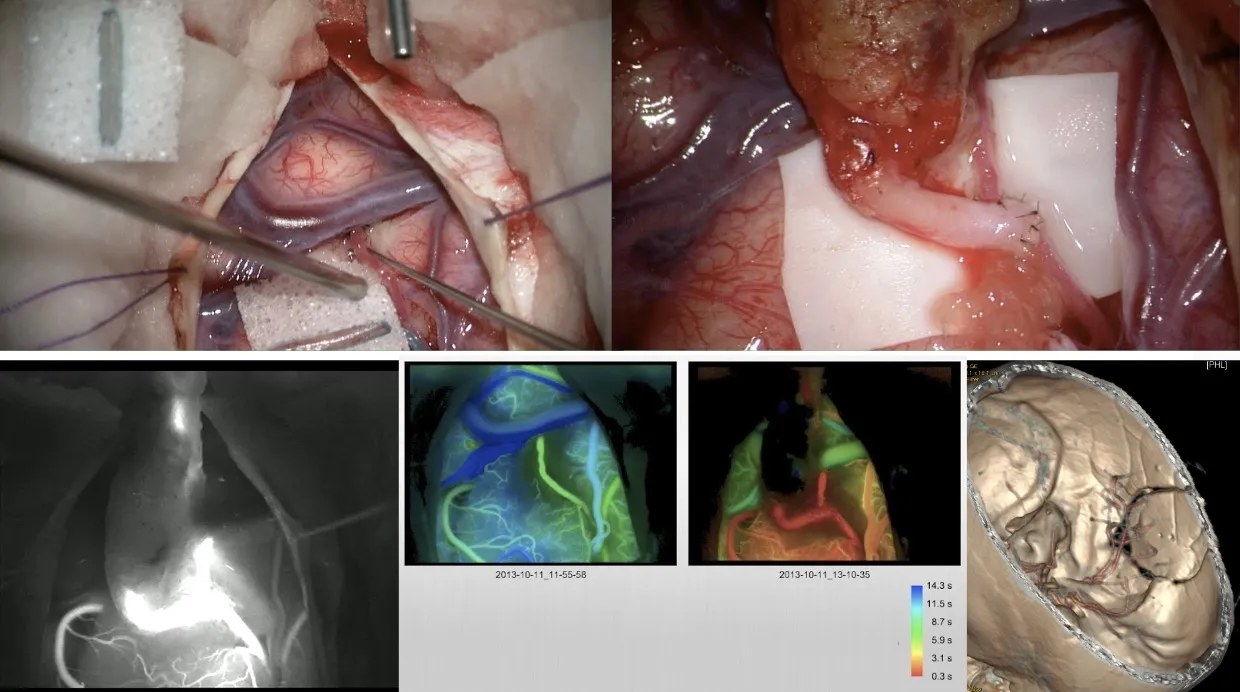

Técnica quirúrgica del clipaje

La cirugía de clipaje de un aneurisma cerebral es un procedimiento de alta complejidad técnica que se realiza con ayuda de tecnología avanzada de control intraoperatorio. Los pasos fundamentales de la intervención son:

- Apertura de la cisura de Silvio (separación del lóbulo temporal del frontal) para acceder a la base del cerebro.

- Disección y exposición del aneurisma.

- Realización de una angiografía intraoperatoria y control con fluorescencia de verde indocianina para visualizar el flujo sanguíneo en tiempo real.

- Clipaje temporal de la arteria portadora del aneurisma para reducir la presión y facilitar la colocación segura del clip definitivo.

- Clipaje definitivo del aneurisma.

- Control mediante fluorescencia de verde indocianina y angiografía para verificar el cierre correcto del aneurisma y la permeabilidad de las arterias adyacentes.

- Cierre de la intervención.